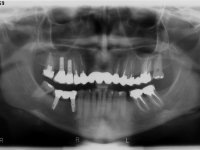

Female patient, 43 years old non-smoker. After a clinical and imaging examination, the patient presented teeth 1.7 / 1.4 / 1.3 / 2.2 / 2.3 / 2.4 / 2.6 with endodontic treatment in the upper jaw, showing absence of teeth 1.6 / 1.5 / 1.2 / 1.1 /2.1 and 2.5, and was rehabilitated with a 10-element monobloc metal-ceramic bridge. The anterior maxilla presented extensive vertical and vestibular bone reabsorption. In the lower jaw, two implants were placed at the site of teeth 4.6 and 4.5 rehabilitated with a metal-ceramic bridge. Teeth 3.6 and 3.7, with endodontic treatment, were rehabilitated with intra-radicular posts and a two-element metal-ceramic bridge. The antero-inferior teeth presented class III and IV resin restorations. Tooth 3.5 was absent. The patient had a vertical dimension of occlusion reduction, accompanied by accentuated dental wear and some ceramic fractures. Good oral hygiene.

In view of the clinical situation, oral rehabilitation was proposed to improve the aesthetic appearance, but also to solve the lack of posterior teeth, seeking a functional and aesthetic rehabilitation. The plan included replacing the metal-ceramic bridge by a bridge with Zr infrastructure coated with coronary and gingival ceramics. The edentulous area of the first quadrant would be rehabilitated with 2 implants and a bridge of two elements. It was intended with this treatment plan, to recover the vertical dimension of the occlusion and to reshape the dental anatomy, thus creating a more natural aesthetic appearance.

Alginate impressions were made at both arches arcades, accompanied by intermaxillary registration relations and collecting information with facial bow facial bow. In the laboratory, a provisional bridge with 13 elements in autopolymerizable acrylic was built, in which a metallic reinforcement was included. Teeth 1.7 / 1.4 / 1.3 / 2.2 / 2.3 / 2.4 and 2.6 were used as pillars. The metal-ceramic bridge was removed after performing longitudinal cuts with diamond burs. The dental abutments were reprepared and the temporary bridge was relined in the mouth with self-curing acrylic. After confection of the provisional bridge, a gingival epithesis was made using composite resin with gingival tonality in order to function as a mock-up, which allowed the patient to preview the possibility of using gingiva shade ceramics in the final work. This option was approved by the patient. Subsequently, the placement of two implants in the first quadrant was planned and executed. The provisional monoblock was removed for placement of the implants, and after surgery was again cemented provisionally. After the osseointegration period, the impressions were made to the maxilla. In the anterior zone, impregnated gingival retraction cords were used, and in the posterior areas, kaolin paste was used. Implant printing utilized the open tray technique. The printing material used was soft and regular putty addition silicone, both fast-setting. In the laboratory, the model of provisional restorations and the gingiva epithesis mock-up served as orientation for waxing the infrastructure. The plaster work model and the waxing of the infrastructure were placed in a laboratory scanner and yielded a digital work model, in which the scanning of the waxed infrastructure was superimposed. This overlay facilitated the CAD design of the Zr infrastructure. Subsequently, the CAD drawing for a CAM milling process provided the Zr pieces. The infrastructure was pigmented with a pinkish coloration, which favors the subsequent placement of gum shade ceramic. During the modeling of the infrastructure, the need to increase the occlusal wear on tooth 1.4 was detected. This was done in the real working model cast and an acrylic wear control guide was created, which accompanied the proof of the infrastructures. Corrective wear and Zr parts test were performed in mouth. During the test, the color choice of the gum shade ceramic was reassessed. The treatment was finished in the laboratory, and after approval by the patient, was definitively placed in the mouth.